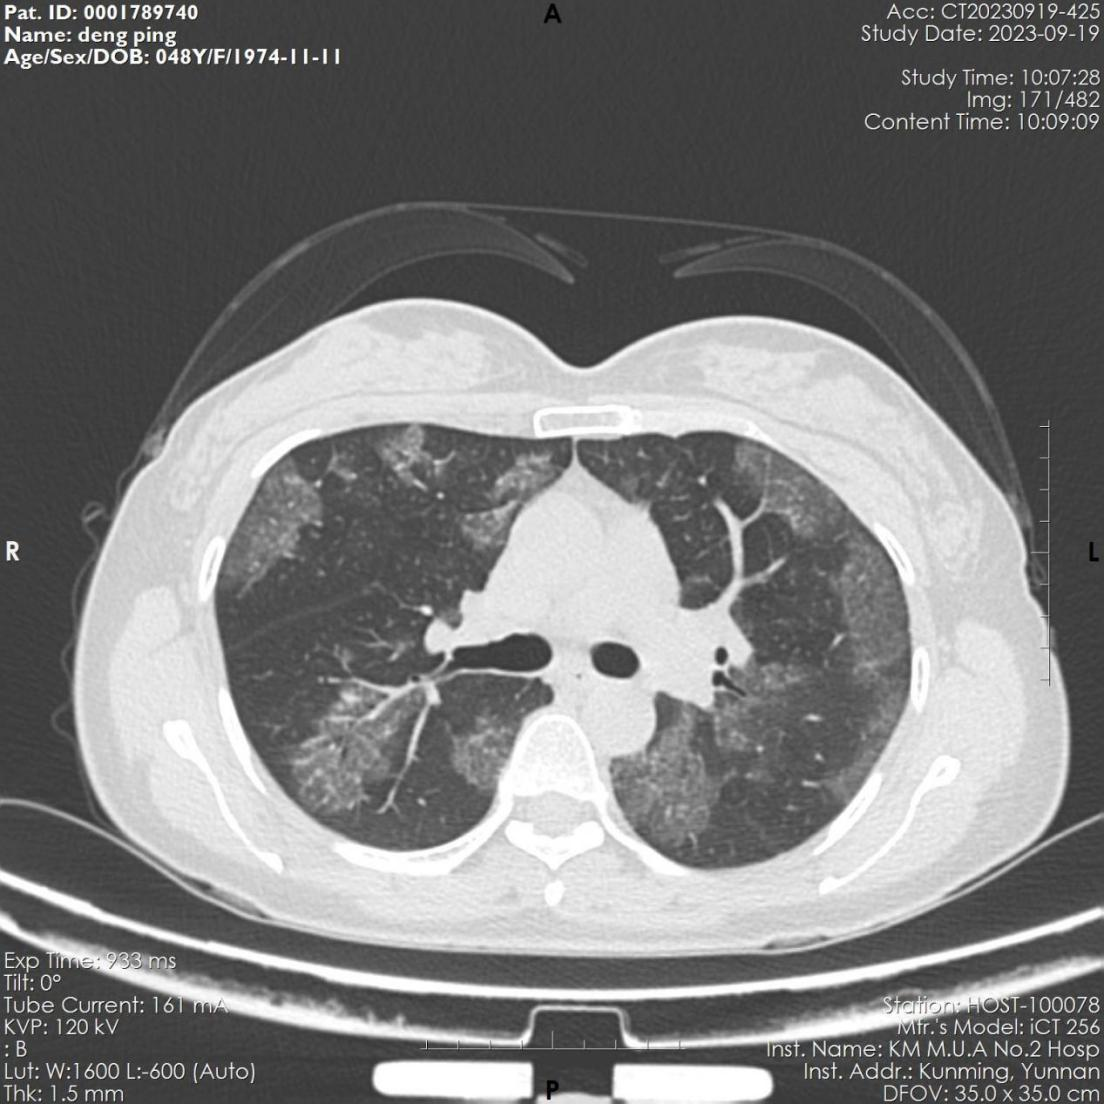

该患者,女,48岁,近3月来反复出现活动后胸闷气促。6月份因感染肺炎住院治疗,经抗病毒治疗后,咳嗽、咽痛等呼吸道症状缓解。9月因胸闷气促再发加重,来到昆医大附二院全科医学科就诊,复查胸部CT显示肺部病变未见吸收,病变呈弥漫磨玻璃影,病变与正常组织分界较清,呈“地图征”,考虑“间质性肺疾病-肺泡蛋白沉积症可能”收住全科医学科。入院后完善电子支气管镜检查示双侧支气管未见明显异常,但各管腔内的肺泡灌洗液呈乳白色,肺泡灌洗液细胞学病理检查示肺泡巨噬细胞中间粉红色颗粒样物质,D-PAS和PAS染色阳性。结合病史、胸部CT、肺泡灌洗液呈乳白色、PAS染色阳性,该患者确诊罕见病“肺泡蛋白沉积症”。

9月26日上午,手术在全科医学科沈雯副主任团队、麻醉手术科欧阳杰副主任医师团队和av线上团队密切配合下开始,患者全麻后,行双腔气管插管,检验密闭性,保证左右肺安全隔离,Y型管对单侧病肺进行多次灌洗。开始灌洗出来的液体浑浊,有较多的沉渣及泡沫,随着灌洗的不断进行,洗出的液体逐渐变得清亮,手术历时3.5小时,全肺灌洗总量为11L,术中患者耐受良好,生命体征平稳。术后患者顺利拔管脱机,状况良好。术后复查肺部病灶明显减少,术后第二天患者出院。